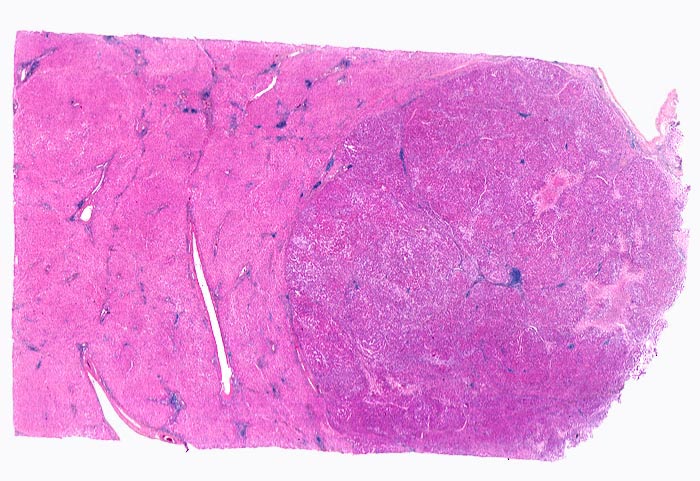

Makroskopisch imponiert das hepatozelluläre Karzinom als solitäre grosse Tumormasse, als zahlreiche zirrhoseartige Knoten oder als scharf begrenzter Knoten mit oder ohne Kapsel. Die tumorfreie Leber ist in der Mehrheit der Fälle zirrhotisch umgebaut. Mikroskopisch bilden die Tumorzellen mehr als 2 Zellen breite Trabekel (> 1237), kompakte Tumormassen (> 1229) oder pseudoglanduläre Strukturen (dilatierte Canaliculi) (> 1212) (> 1199). Desmoplastisches Bindegewebe fehlt meist. Innerhalb des Tumors fehlen Portalfelder. Es finden sich lediglich Arterien. Etwa bei der Hälfte der Karzinome lässt sich intrazytoplasmatische oder intracanaliculäre Galle (> 1238) nachweisen. Immunhistochemisch lassen sich mit einem polyklonalen Antikörper gegen Carcinoembryonales Antigen (CEA) Gallecanaliculi zwischen den Tumorzellen nachweisen. Die Tumorzellen bilden keinen Schleim.

• Scharf begrenzter bekapselter Tumor.

• Innerhalb des Tumors Blutgefässe, aber keine Portalfelder.

• Die Tumorzellen bilden Trabekel, welche überwiegend mehr als 2 Zellen breit sind und Pseudodrüsen.

• Sinusoidartige Blutgefässe mit Endothelauskleidung verlaufen zwischen den Trabekeln und den Pseudodrüsen.

• Die Tumorzellen erinnern an normale Hepatozyten, sind aber kleiner als die Hepatozyten und die Kern-Zytoplasmarelation ist deutlich erhöht. Das Zytoplasma ist basophiler als das der angrenzenden Hepatozyten.

• Galle ist sichtbar in den Pseudodrüsen.

• Tumorfreies Parenchym mit chronischer viraler Hepatitis (B und D): dichtes chronisches Entzündungsinfiltrat in den Portalfeldern übergreifend auf das Parenchym (Interfacehepatitis). Spärliche intralobuläre Entzündung mit Einzelzellnekrosen (Apoptosen). Fibrose der Portalfelder mit Septenbildung und unvollständigem zirrhotischem Umbau.

Geringe gemischttropfige Verfettung des Leberparenchyms.